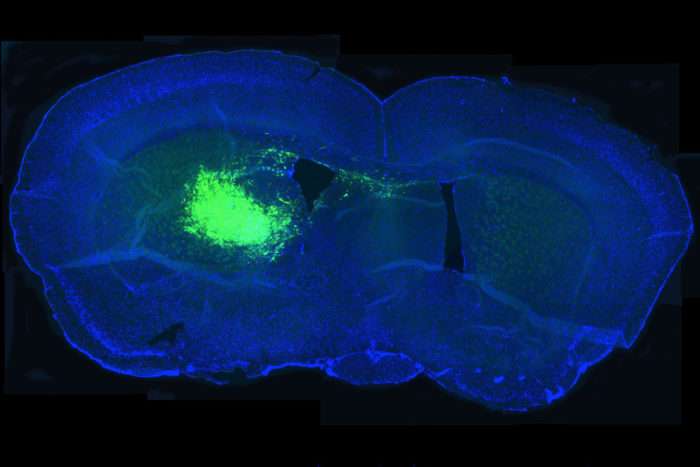

La nuova ricerca ha dimostrato che i pazienti con glioblastoma con elevata espressione di un gene che codifica per NAD + conosciuto come NAMPT, sono morti prima. I tumori con elevata espressione dello stesso gene sono cresciuti rapidamente quando sono stati impiantati nei topi e si sono ridotti quando NAMPT è stato inibito.

Utilizzando cellule di glioblastoma umano, Kim, Amit Gujar e colleghi, hanno dimostrato che NAMPT aiuta le cellule staminali cancerose a sopravvivere e proliferare, alimentando la crescita di tumori già esistenti, mentre l’ inibizione di NAMPT riduce la capacità delle cellule staminali tumorali di svilupparsi.